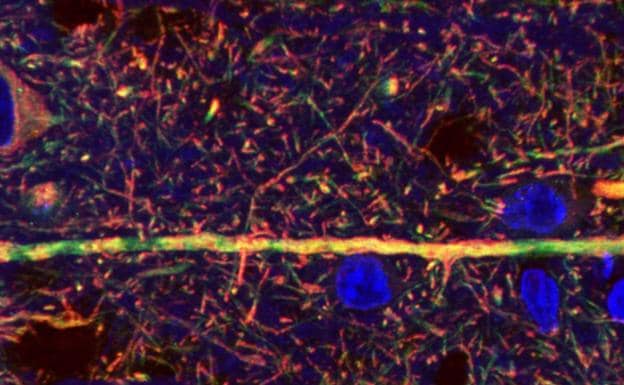

En un intento por descifrar las bases celulares de los efectos de la marihuana, un estudio ha observado que esta planta provoca efectos terapéuticos o adversos según la región celular que activen